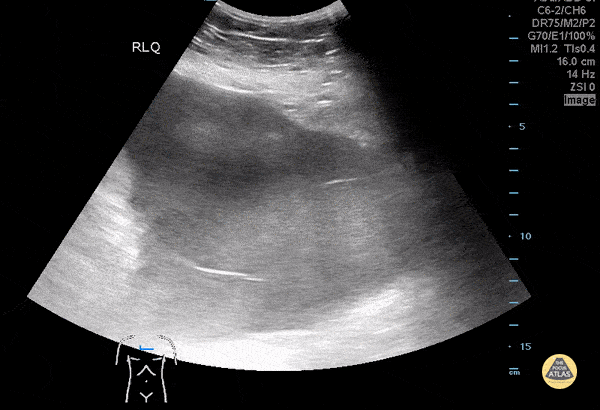

Bowel-GI - Complex Ascites

A 70 year old male with history of pancreatic cancer presented with abdominal distention. POC US demonstrated complex ascites. As seen in this clip, complex ascites (such as from malignancy) often demonstrates loculations as well as layering due to dense particulate (exudative ascites) within the fluid. Mario Corro, MD, PGY-3 Staten Island University Hospital